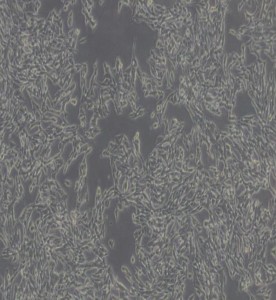

TT人甲狀腺導(dǎo)管癌細(xì)胞

中文名稱 : 人甲狀腺癌細(xì)胞

細(xì)胞簡(jiǎn)稱 : TT

細(xì)胞形態(tài) : 上皮細(xì)胞樣

生長(zhǎng)特性 : 貼壁細(xì)胞

TT細(xì)胞是從77歲女性甲狀腺髓質(zhì)癌患者的穿刺活檢樣本中建立。TT細(xì)胞持續(xù)產(chǎn)生高水平的降血鈣素和C E A ,在更換培養(yǎng)基后24小時(shí)和72小時(shí)在培養(yǎng)基中檢測(cè)到的免疫活性的降血鈣素濃度分別為3900pg/百萬細(xì)胞和7700pg/百萬細(xì)胞。72小時(shí)后,C E A 積累濃度超過27ng/百萬細(xì)胞。